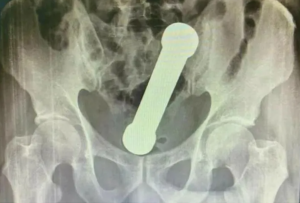

Os médicos encontraram o peso de dois quilos, de cerca de 20 centímetros de comprimento, como os que são usados em academias de ginástica para exercícios de braço, ao realizarem um exame de raio-X. O halter estava entre o reto e o intestino grosso do paciente.